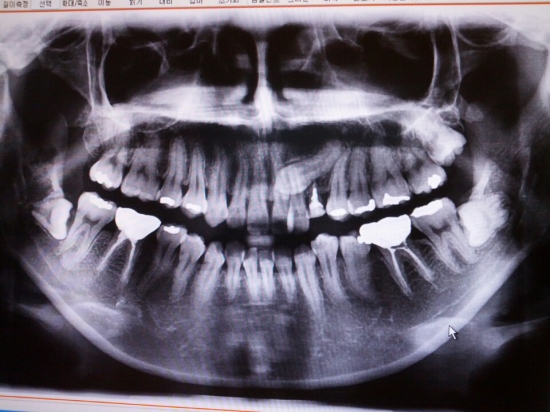

안녕하세요 답변 부탁드립니다.[치아 사진 첨부]

안녕하세요 많은 분들이 질문 남기시는데도 정성스럽게 답변 남겨주시느라 수고가 많으시네요 ㅜㅜ 20대 후반 직장인입니다. 어릴 때부터 교정을 너무 하고 싶었는데 여러 이유로 미루다 이제 정말 더 늦으면 안될 거...